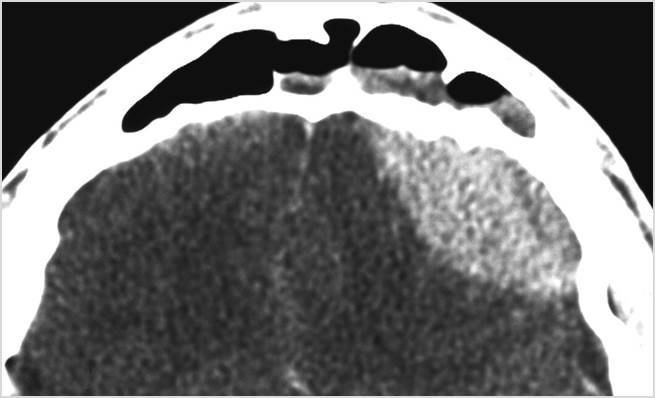

There is brain edema specifically involving the frontal and temporal lobes. [Yes/No]

There is cerebritis specifically involving the frontal and temporal lobes. [Yes/No]

There is brain abscess specifically involving the frontal and temporal lobes. [Yes/No]